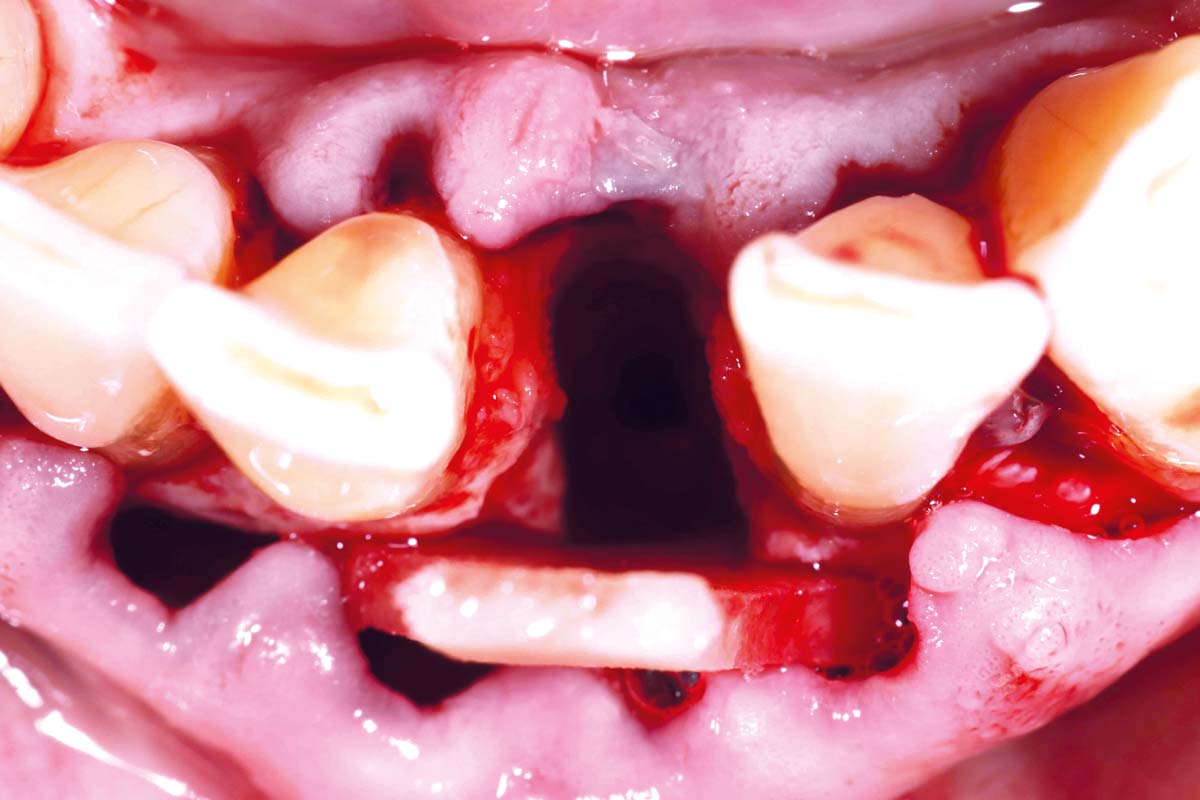

Multiple socket preservation in the mandibular with collacone® max – Dr. D. Jelušić

Pre-operative x-ray image, teeth 43, 44, 45, 46 and 47 planned for extraction